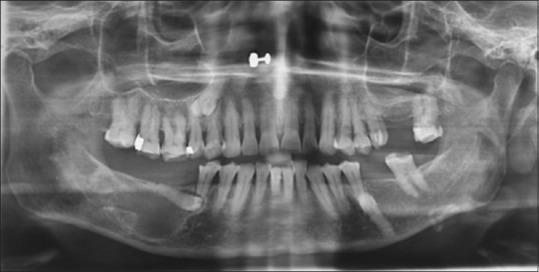

Odontogenic keratocyst(OKC)is a cyst oftooth origin with an aggressive behavior including a high recurrence rate, it has been rechristened to keratocystic odontogenic tumor(KCOT) as it be the reflects its neoplastic nature. We report a case of KCOT in association with an impacted supernumerary tooth along with Trigeminal Neuralgia, that subsided by itself after removal of the cyst.